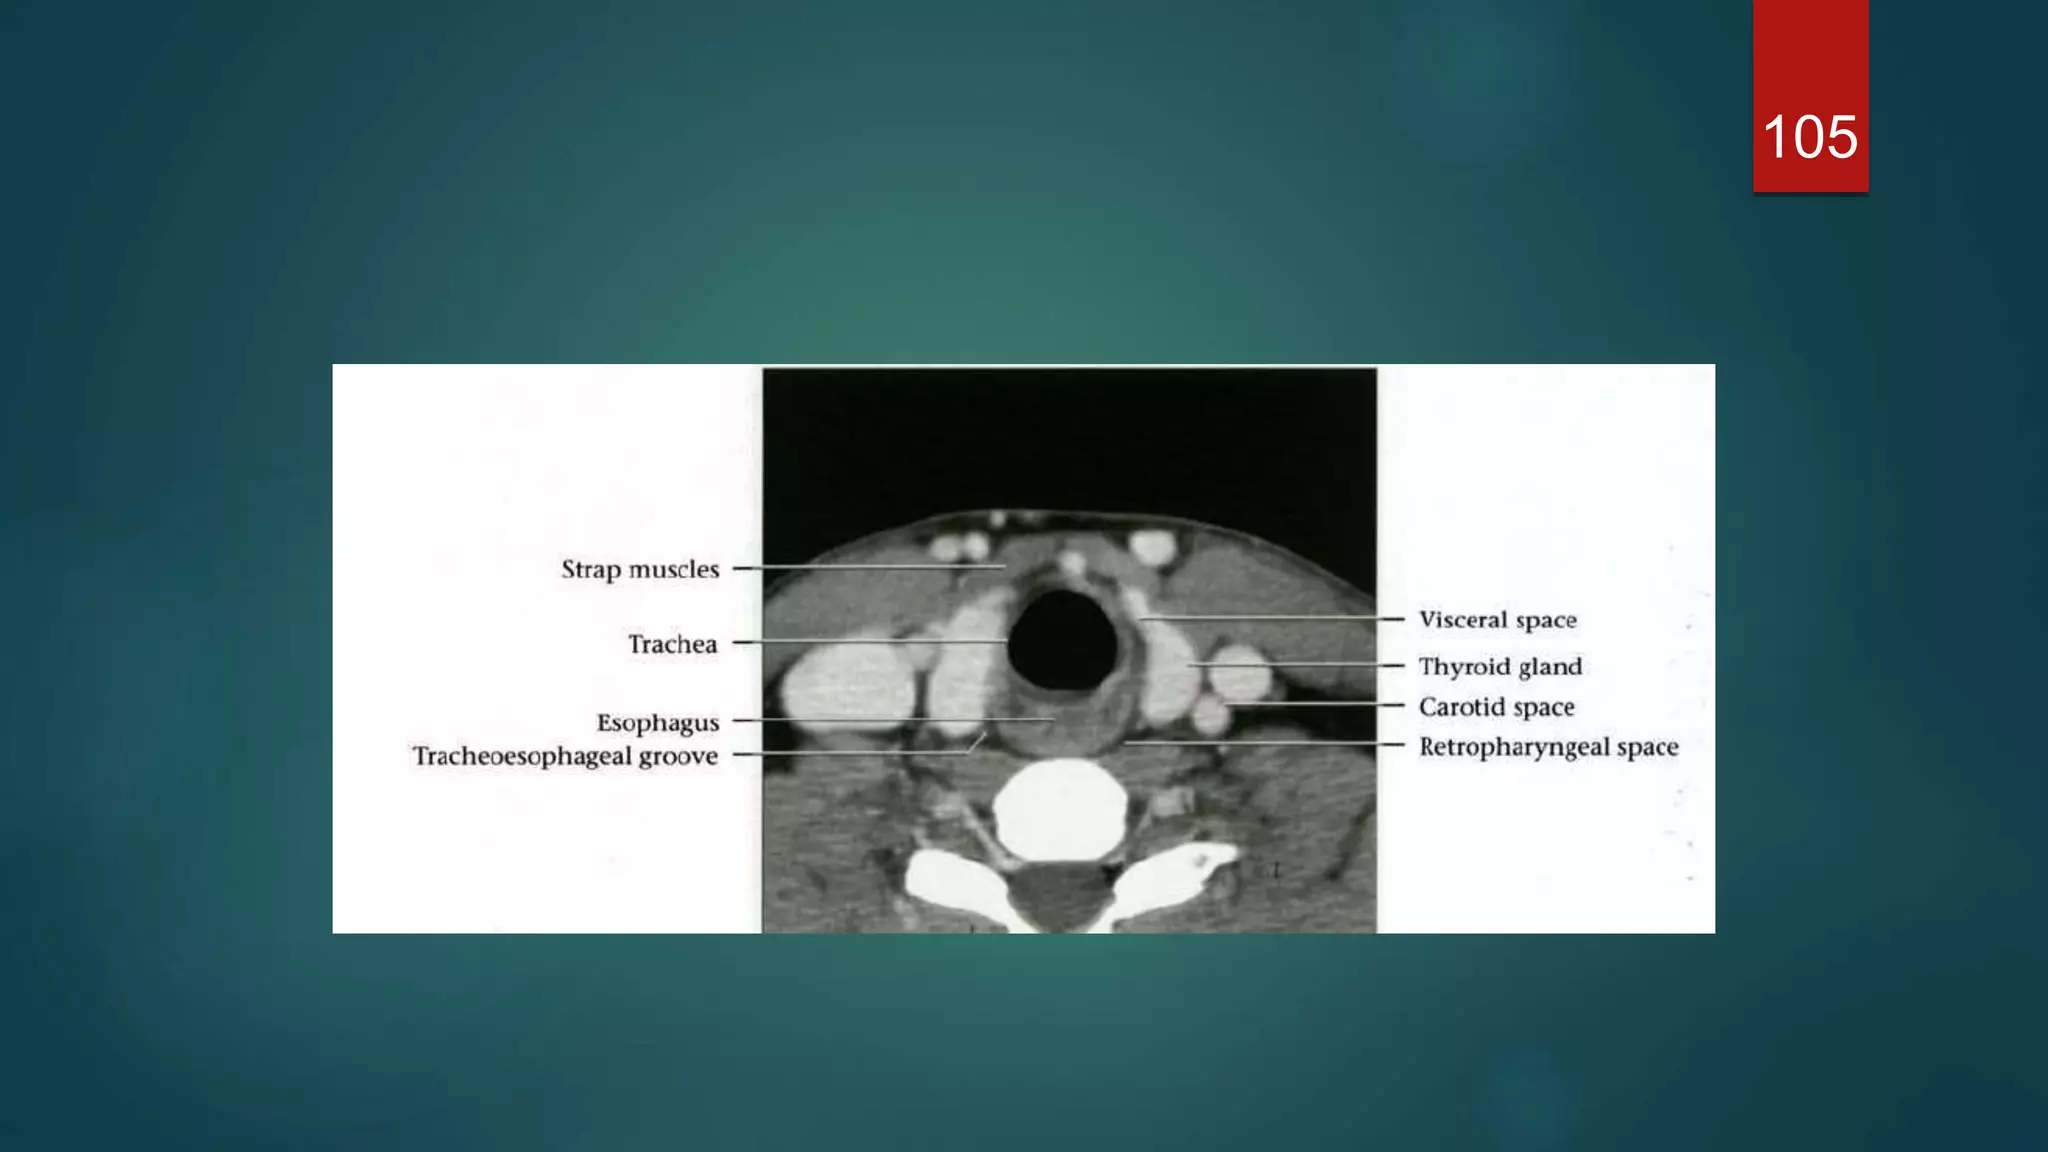

Cervical trachea and esophagus

105

Visceral space  Thevisceral space extends from the hyoid bone to the superior mediastinum (level of aortic arch / T4), and is surrounded by the middle layers of the deep cervical fascia.  Extend from hyoid bone to superior mediastinum  Contents • thyroid gland • parathyroid gland • oesophagus • larynx • hypopharynx • trachea • recurrent laryngeal nerve • lymph nodes (level VI)

 The thyroidgland consists of two lateral lobes joined by a midline isthmus, and lies anterior and lateral to the trachea.  The lobes extend from the thyroid cartilage superiorly to the sixth tracheal ring inferiorly  Posterolaterally are the neck vessels, Behind these, on either side, are the prevertebral muscles  Anterior to the gland are the strap muscles of the neck and the sternomastoid muscles 57